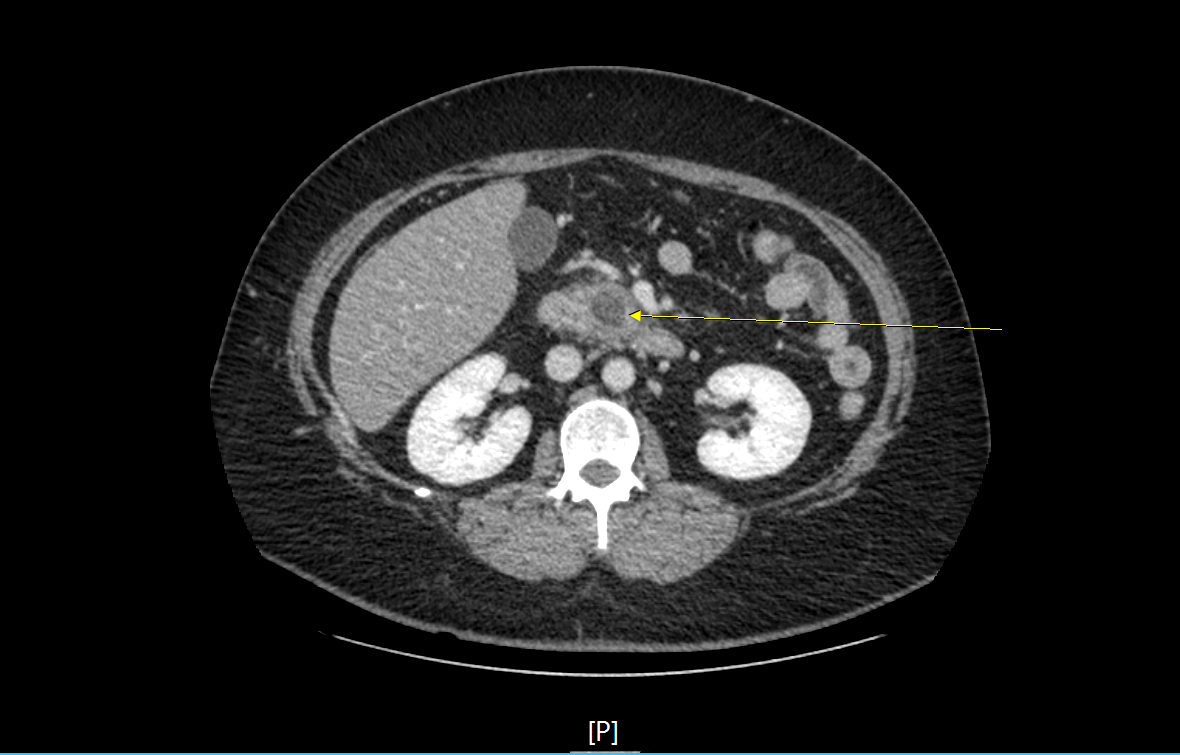

2-3. 영상검사에서 전형적인 소견

1) 복부 전산화단층촬영(CT), 자기공명영상(MRI), 복부 초음파(abdomen USG/SONO)

2) 복부 전산화단층촬영 : 급성 췌장염의 진단에 가장 중요한 영상검사로 혈청 amylase가 정상인 경우 췌장염의 진단에 필수적이다. 영상 소견을 통해 췌장의 괴사, 가성낭종(pseudocyst), 췌장성 복수와 같은 합병증도 함께 확인할 수 있어 유용하다.

3-2. 영상소견에 따른 분류

2) 괴사성 췌장염 (necrotizing pancreatitis)

- 염증으로 인한 췌장실질 및 췌장주위조직의 괴사

- 이미 괴사된 조직으로 조영제에 의해 조영증강 되지 않음.

- 국소 합병증으로 췌장 주변으로 궤사조직이 저류 되는 necrotic collection을 보이거나, 췌장괴사조직이 벽을 형성한 경우 walled-off necrosis소견을 보이기도 한다.

4-4. 복부 전산화단층촬영(Abdomen CT)

- 경증 췌장염에서는 불필요.

- 전형적인 증상 발생 4일 이내 시행하는 경우 타 질환으로 진단되는 경우는 거의 없으며, 괴사 여부, 합병증 여부 판정에 도움을 주지 않는다.

- CT를 시행해야 하는 경우

1) 췌장염의 진단이 불확실할 때

2) 중증(severe) 췌장염인 경우

3) 보존적 치료에 반응이 없거나 악화되어 중재 치료(Intervention)가 필요한 경우

- 가능하면 췌담도 질환에 대한 변별력을 높이기 위해 arterial, portal, venous phase를 촬영하는 3-phase CT의 촬영을 추천함.